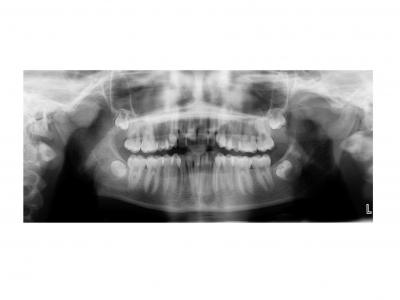

Voici les deux patientes traitées

Ici, dans les deux cas, les deuxièmes prémolaires ont été extraites et les traitements ont duré 18 mois.

Dans le premier cas, la béance s'est fermée spontanément (pas prévu au départ) sans rééducation, sans appareil de contrainte linguale, ni élastique. Il semblerait que le gain de place a permis aux incisives de se redresser spontanément et donc de fermer la béance. La fermeture de la béance, la normalisation de l'environnement anatomique a permis à la langue de se mettre à travailler correctement. Pour le sens transversal, la correction a été aussi spontanée. Juste une minivis dans le secteur 1 a été placée pour recentrer mon milieu (ancrage maximal recherché au départ). Les finitions auraient pu être meilleures. Elle finit avec une légère classe II (on va dire qu’elle est surcorrigée :)). Le traitement a terminé plus tôt que prévu (24 mois annoncé), car problèmes de santé.

Si on n'avait pas extrait dans le premier cas, cela imposait une ouverture de l'espace de la 24 et donc une avancée des incisives supérieures et donc une aggravation de la béance. Dans le deuxième, on sortait les racines de l'os alvéolaires (racines déjà apparentes au départ). Même une expansion associée à du stripping et une distalisation des secteurs latéraux n’auraient pas permis de préserver ce parodonte fin.